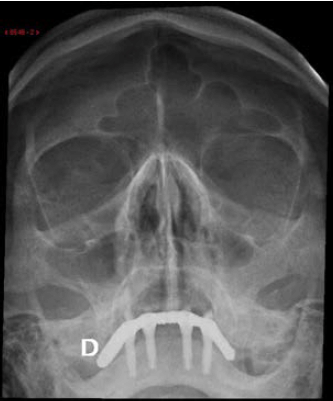

Uma paciente de 60 anos realizou radiografia de seios da face com queixa de cefaleia. Frente às imagens, considera-se que há:

A

sinusopatia aguda, com níveis hidroaéreos nos seios maxilares e velamento de células etmoidais, e doença hipofisária com aumento de volume selar.

B

sinusopatia crônica, com espessamento mucoso nos seios maxilares e células etmoidais, e lesão expansiva da parede posterior do cavum.

C

pólipos nos seios maxilares e células etmoidais, e aumento do espaço articular atlanto-odontoide, provavelmente por artrite reumatoide.

D

espessamento mucoso dos seios maxilares e lesão insuflante do palato, provavelmente por hiperparatiroidismo secundário.

E

sinusopatia aguda, com níveis hidroaéreos nos seios maxilares, e esclerose da asa do esfenoide, podendo corresponder à meningeoma à direita.